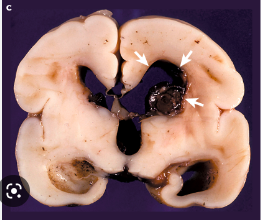

Describe the pathology of Intraventricular hemorrhage / periventricular leukomalacia: What birth weight babies most likely? [1] What is pathophysiology? [1] Which disease is a risk factor for this? [1]

Intraventricular hemorrhage / periventricular leukomalacia: * **VLBW** (less than 1500g) at greatest risk * **Resp. distress syndrome** 4x more likely * Pathology: **blood vessels** in the preterm may be **more** **fragile** and immature and cause **small to large bleeds in brain ventricles**

What does Intraventricular hemorrhage / periventricular leukomalacia look like on ultrasound? [1]

Honeycombed